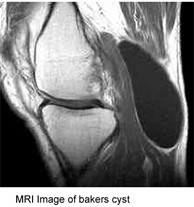

Orthopedic Surgery

Sports Medicine

MRI image of bakers cyst